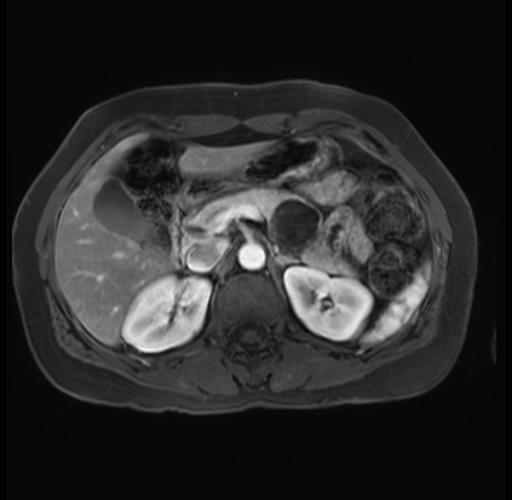

Imaging Analysis

Look through the patient's CT scan to identify any areas of concern for the necessary procedure.

Based on your CT findings, which issue(s) are present and would give reason for "planned slowing down moment(s)" in this case?